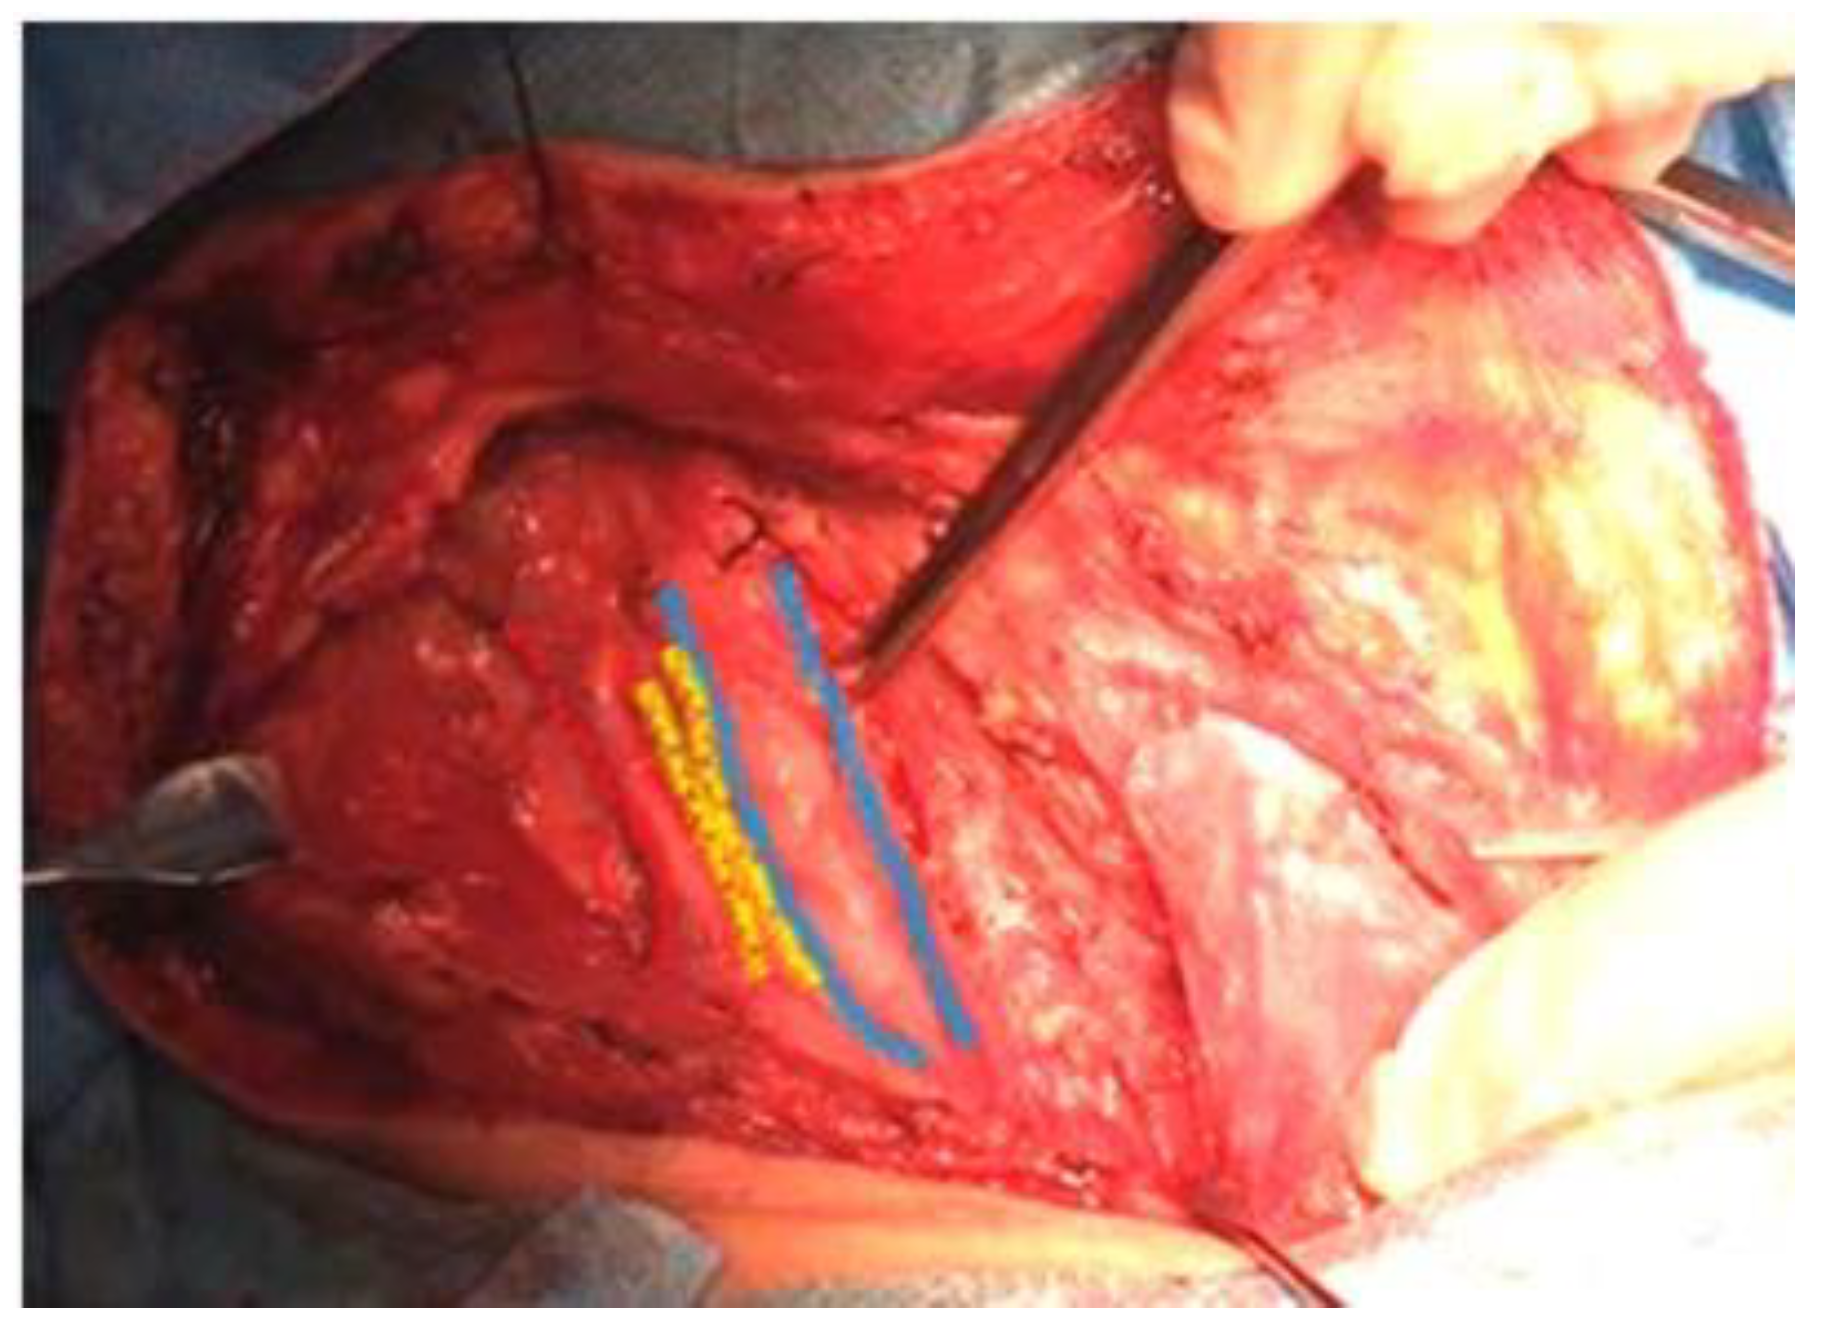

![]() |